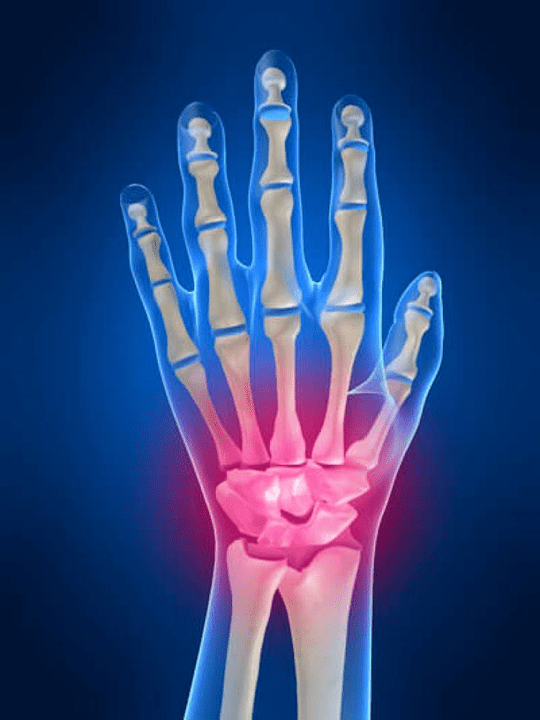

Eskuko artikulazioen anatomia

Eskuko juntura guztiak ohartarazten dira talde hauetan banatzeko:

- eskumuturreko juntura;

- eskumuturreko artikulazioak;

- Carpal-patroiaren artikulazioak;

- Interpencial artikulazioak;

- Phalanx artikulazio parlemonalak;

- Interphalanx artikulazioak.

Eskumuturreko artikulazioa

Eskumuturreko artikulazioa hezur proximalen hezurrak osatzen dute (goiko) eskumutur ugari (trihedral, erdi -munon, hezur scaproideak) eta erradiazio eta ukondoko hezur distalak. Ukondoaren hezurra ez da zuzenean eskumuturreko hezurrekin lotuta, baina distalaren laguntzarekin (Beheko) disko artikulatua. Egitura honek eskumuturreko junturaren barrunbea bereizten du barrunbe distaletik (Beheko) Fitxa artikulazioa.

Eskumuturreko artikulazioak

Eskumuturreko artikulazioak hiru artikulazio motaren arabera irudikatzen dira. Lehenengo formak goiko hezurren artean kokatzen diren artikulazio horiek biltzen ditu (Escapoidea, erdi -munea, trihedrala, ilarra) edo beheko errenkada (kako formakoak, buruko burua, trapezioidea, hezur-harrapaketa). Artikulu hauek Interchangena artikulazioak deitzen dira. Bigarren motaren arabera, erdiko idatzitako artikulazioa sailkatuta dago. Joint honek S formako forma du eta eskumuturreko goiko eta beheko errenkadaren hezurrak konexioaren ondorioz sortzen da. Hirugarren motak ilar hezurraren artikulua biltzen du. Artikulazio honen bidez, hezur trihedrikoa ilar hezurrarekin lotuta dago.